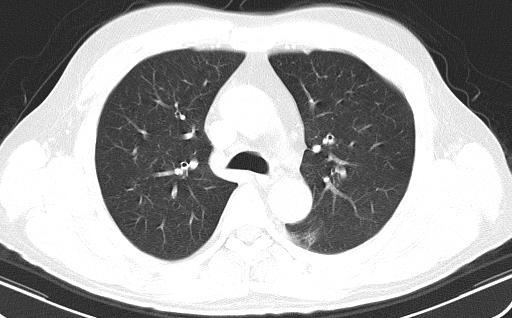

收集过上呼吸道标本、下呼吸道标本,检测过C反应蛋白、降钙素原和白介素-6,检测过新冠抗体,做过胸部影像检测,甚至曾经有一段时间胸部影像“毛玻璃样”纹理被当成确诊新冠的金标准。